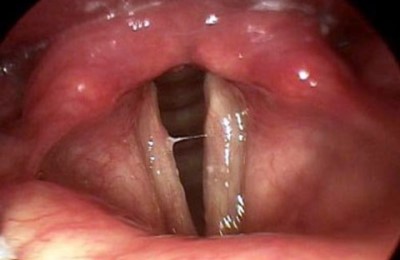

Щитовидная железа находится в непосредственной близости, «охватывая» своими долями ее с боков. Гортань (ее полость) делится на три отдела. Первый из них – преддверие, второй – межжелудочковый, третий – подголосовая полость. Очень важным является тот факт, что именно в гортань отвечает за работу голосовых связок и голосовой щели.

Самый распространенный вид воспаления – острый ларингит катарального характера. Его симптомы – охриплость голоса, ощущение першения, субфебрильная или нормальная температура, дисфония и мучающий сухой кашель.